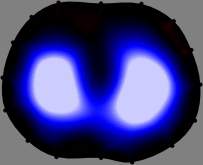

Figs. 3 and 4 compare the performance of the proposed FER method in (20) with the standard regularized least-squares method ((19) when is the identity matrix). The regularization parameter of the standard method was heuristically chosen for its best performance, and the parameter of the FER method was set to be one of three different values . The injection current was 1 mA at 100 kHz, and the frame rate was 9 frames per second. The reference frame at was obtained from the maximum expiration state. The measured data, , represent the voltage differences between each time and . The blue regions, which denote where conductivity decreased by inhaled air, increased during inspiration and decreased during expiration. The FER method with was clearly more robust than the standard method that produced more artifacts originated from the inversion process.

| Standard | |

||||||||||

| FER () | |